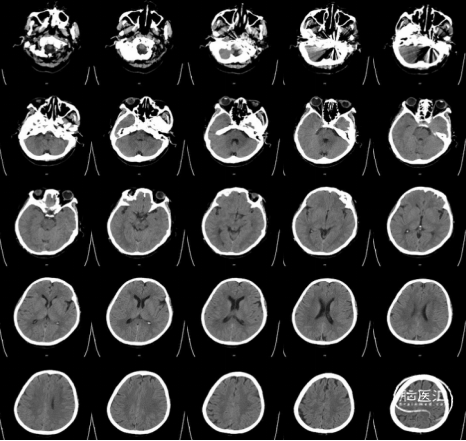

栓塞术后即刻CT未见颅内出血或Onyx胶异位栓塞。麻醉复苏后患者诉耳鸣消失,未诉其他不适,查体无新发神经系统体征。术后第二日,复查CT未见异常(图7),患者顺利出院。